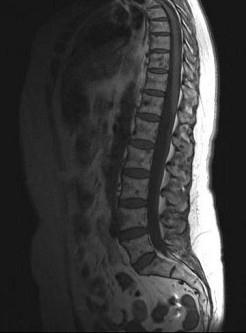

问题 女,57岁,背部隐痛1个月余,请结合影像学检查,选出最可能的诊断 ( )

选项 A、椎体压缩骨折 B、脊椎转移瘤 C、脊椎结核 D、强直性脊柱炎 E、化脓性脊柱炎

答案 B